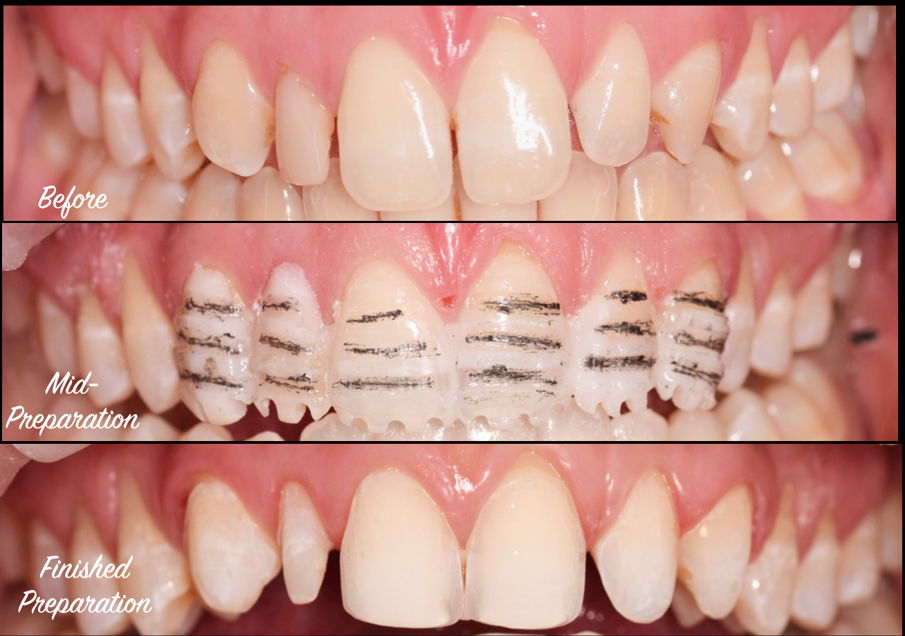

Post-ortho provisional retention was implemented with removal essix retainers which were used for home whitening of the upper and lower teeth. A final shade of BL3 was achieved, after 10 days of rehydration. In this time the lab created a diagnostic wax up guided by the smile design. A putty matrix was used to transfer the wax up to a trial smile (Fig. 2).

Once the trial smile was approved by both patient and dentist, the acrylic was used as a guide for crown lengthening on the UR2, and then as a preparation guide for the APT technique (Fig. 3a-d).